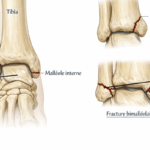

Traumatismes fréquents : entorses, foulures et micro-fractures méconnues

- Une entorse mal soignée peut créer une instabilité chronique.

- Certaines micro-fractures passent inaperçues à la radiographie initiale.

- La compensation musculaire entraîne des douleurs projetées vers le haut.

⚠️ Exemple : une entorse externe du ligament latéral peut provoquer une inflammation du tendon péronier latéral, douloureuse jusqu’au mollet.

Radiographie de la cheville et du tibia

- Elle permet d’exclure une fracture, un arrachement osseux ou une arthrose articulaire.